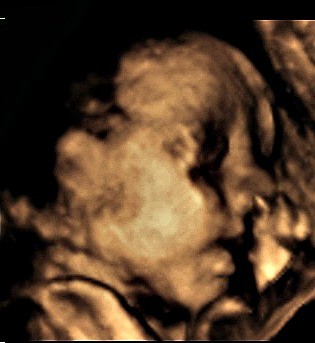

jak wróciliśmy to poszedł spać a dzisiaj znowu obudził mnie kopniakami i chyba się przeciągał bo czułam tak jakby rękę albo nogę miał wbitą w mój brzuch i taką małą gulkę.. Jak ja go już kocham :-)